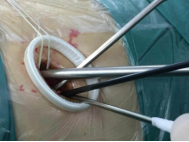

较两孔、多孔胸腔镜手术或传统手术,单孔手术具有创伤更小、出血更少、术后疼痛更轻、瘢痕小、切口更加美观、术后恢复快、住院时间短等优势。但手术中所有器械(包括观察镜、吸引器、电凝钩、切割闭合器、双关节等各种操作器械)都要是从一个小“孔”进入,器械之间的互相干扰,同时器械与观察镜几乎平行,视野非常狭窄,手术难度明显,增加极其考验医生的技术。

器械进入小孔。